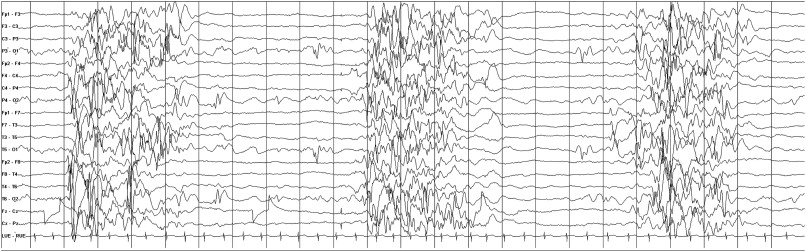

• 뇌파 검사 (EEG): 첫 단순 열성경련 후에는 권고되지 않음. 복합 열성경련이거나, 향후 뇌전증으로의 발전이 우려되는 경우 고려할 수 있음.

• 뇌파 (EEG): 각성 및 수면 시 모두 억제-발현 (Burst-suppression) 패턴을 보임.

• 뇌파 (EEG): 오타하라 증후군과 동일한 억제-발현 (Burst-suppression) 패턴

• 3대 특징: ①다양한 형태의 발작 (특히 강직 발작), ②심각한 인지 기능 장애, ③뇌파의 전반성 완만 극서파 복합체 (<2.5Hz) 및 GPFA

• 뇌파 (EEG): 특징적인 전반적 3Hz 극서파 복합체

• 뇌파 (EEG): 특징적인 중심-측두부(Centrotemporal) 극파

• 4~6Hz 의 다극서파